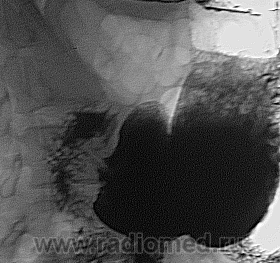

Полученная "теневая симптоматология" весьма основательно свидетельствует о "раковом поражении" нижней трети пищевода с распространением процесса на желудок.

Дело в том, что как не удивительно, а эндоскописты всё же промахнулись мимо опухолевых клеток, в гистологии нет их, морфологи по рекомендовали повторный забор биоптата. Случай тоже свежий, получается что уже вчерашний. Если внимательно посмотреть то по малой кривизне идёт "голое плато", рельефа слизистой нет, стенка регидна и это тянется до с/3 тела желудка. Задействована субкардия и частично кардиальный отдел, о диференцировки пищеводно-желудочного перехода не идёт и речи. Я выставил"кардио-эзофагиальный рак, смешенная форма", но почему то у меня есть сомнения и хотел бы узнать мнение большинства, правильно ли это? Но вплане то, что там есть рак это факт.